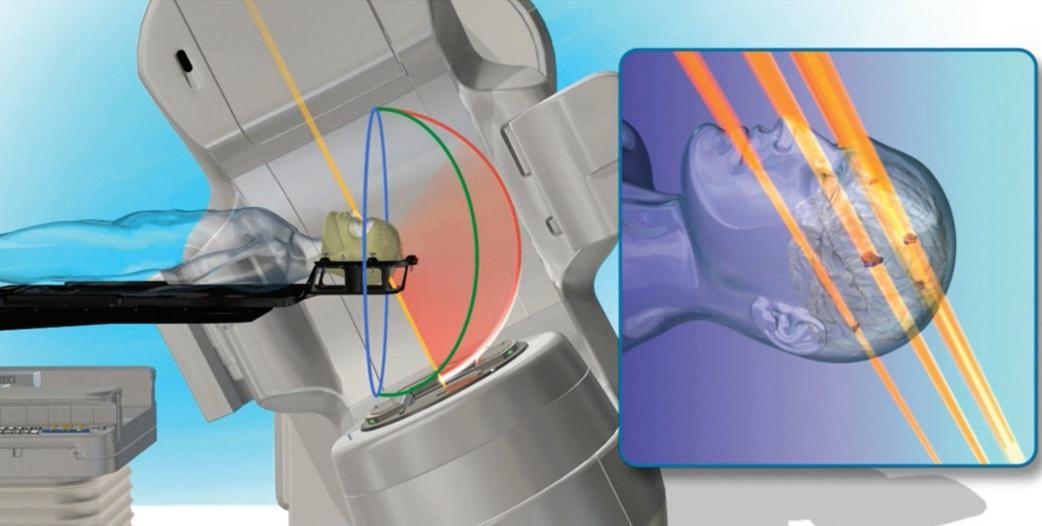

定位放射線治療専用アプリケーション(HyperArc)

HyperArc(ハイパーアーク)は、多発性脳腫瘍に対する高精度な定位放射線治療(SRS/SRT)を、自動化されたワークフローにより短時間かつ安全に実施するシステムです。TrueBeam Edgeに搭載されており、自動化された照射プロセスによって、短時間で高精度な治療を行うことが可能です。

ノンコプラナー(非共面)照射と専用アルゴリズムを用いることで、腫瘍に高い線量を集中させながら、周囲の正常な脳組織への線量を低減し、治療後の有害事象(認知機能低下や脳壊死)のリスク軽減を目指します。

また、複数個(10~20個以上も可能)の腫瘍を一度に治療することができ、治療時間の大幅な短縮が期待されます。さらに、VMATの技術を用いることで、複雑な形状の腫瘍に対しても高精度な治療が可能です。